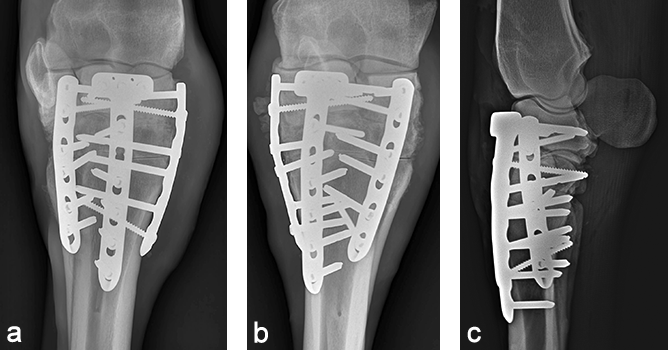

The cast was removed 24 hours postoperatively, and a Robert- Jones bandage with caudal and lateral splints was maintained for 1 month. The mare made excellent postoperative progress with immediate full weightbearing on the operated leg. At 5 months postoperatively, radiographic evaluation confirmed excellent healing of the fracture and almost complete fusion of the middle carpal and carpometacarpal joints with preservation of the radiocarpal joint (Fig 8). At one year postoperatively, the mare showed a very good cosmetic aspect of the carpus, as well as an excellent locomotion at three gates, with only minor mechanical lameness due to reduction of carpal flexion (Fig 9).